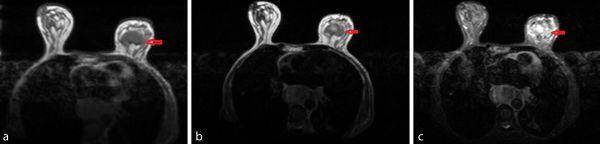

A "breast-oesophagus syndrome" has been described previously, wherein breast carcinoma metastasizes to the inner layers of the oesophagus. The entity is extremely rare, but rarer still is metastatic breast carcinosis from oesophageal cancer (EC), a clinical event that might be termed as "reverse breast-oesophagus syndrome". Considered as the sixth most lethal malignancy, 50% EC patients present with metastatic disease. However, they rarely ever metastasize to the breast. For that reason, a malignant breast mass, which develops following EC, is often thought of as a second malignancy. We report a 62-year-old female who had EC, who was treated with oesophagectomy 2 years ago, and represented with a painful left breast mass. Radiological evaluation revealed suspicious findings (breast imaging-reporting and data system score of 4C), while cytology demonstrated squamous pearls, consistent with metastatic squamous cell EC, which probably disseminated to the breast at the time of surgery. She was treated with local excision of the breast mass, which is the treatment of choice in isolated metastasis to the breast. Such an unusual presentation reminds us that, in any "radiologically suspicious" breast lesion in patients with a history of carcinoma of the oesophagus, the possibility of breast metastasis must not be negated.

摘要